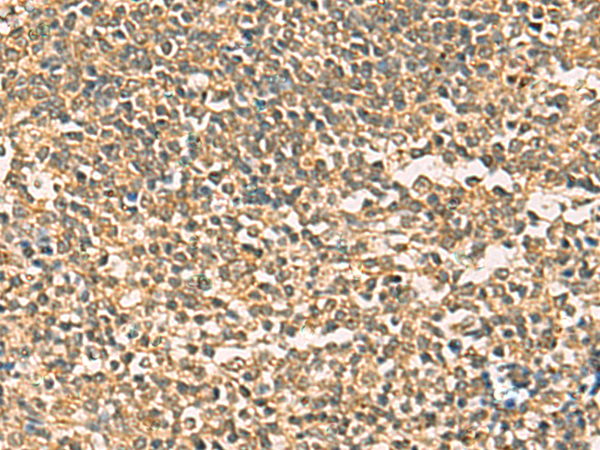

分类: 科研抗体货号: P03354别名: ICF45; IHG-1; hTHG1应用: IHC反应种属: Human, Mouse, Rat